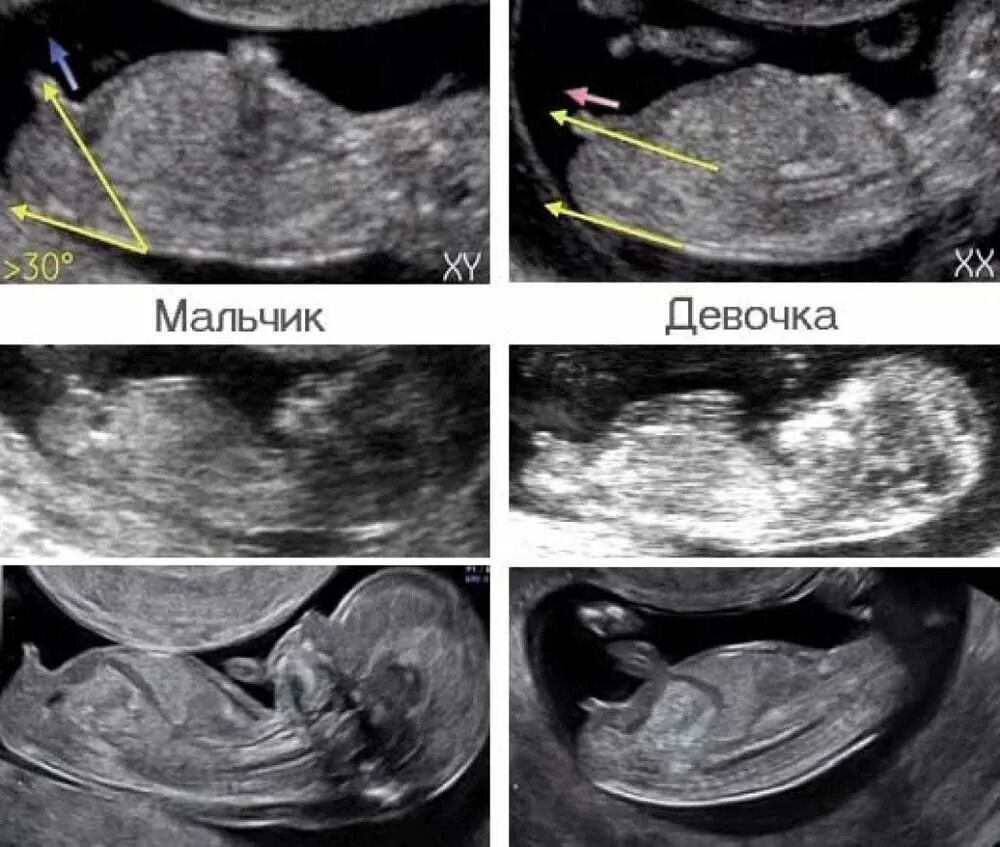

Как на узи выглядит мальчик и девочка